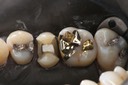

Mark Chun #14 caries removal